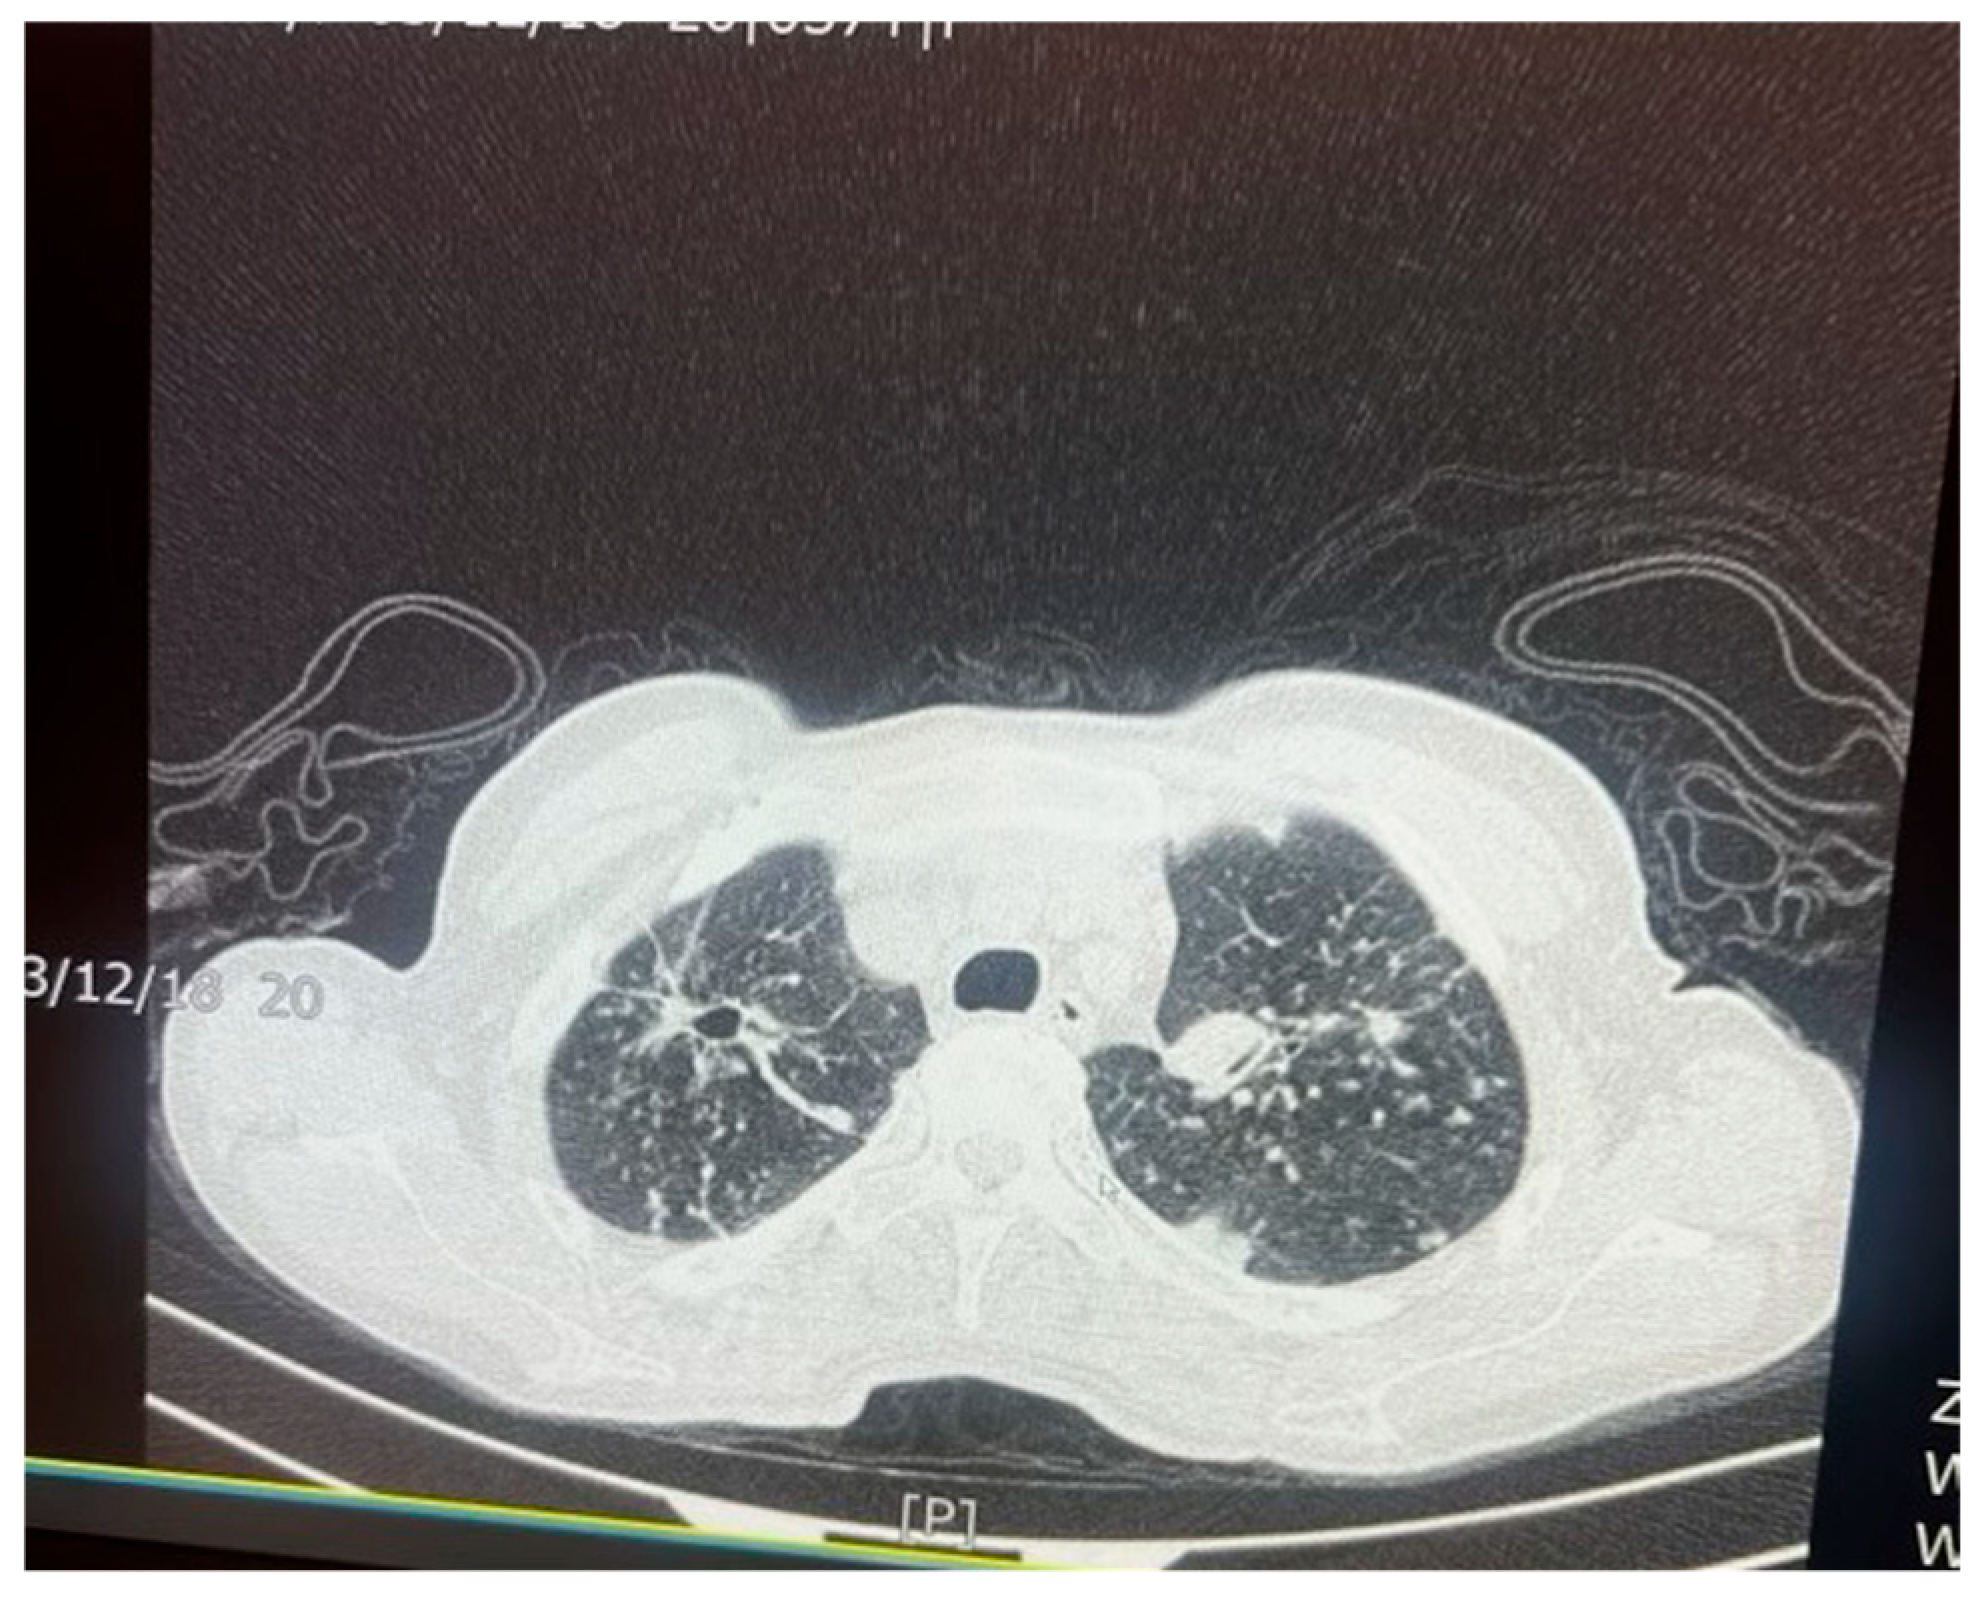

Figure 5. An axial chest CT scan of a 57-year-old female patient with pulmonary TB, showing bilateral pulmonary cavities and multiple nodules. The cavities are seen predominantly in the upper lobes, with irregular thickened walls, suggestive of active TB. The nodular lesions surrounding the cavities represent granulomatous inflammation, which is characteristic of TB infection. These findings are typical of post-primary TB in adults.

Figure 6. An axial chest CT scan of the same patient in Figure 5, demonstrating advanced nodular and cavitary changes in both lungs, consistent with pulmonary TB. The bilateral upper lobe cavities are clearly visible with associated nodules. The distribution of the lesions, with upper lobe involvement and cavitation, is indicative of reactivation of TB. Additionally, areas of tree-in-bud appearance suggest bronchogenic spread of the infection, which is common in TB patients.